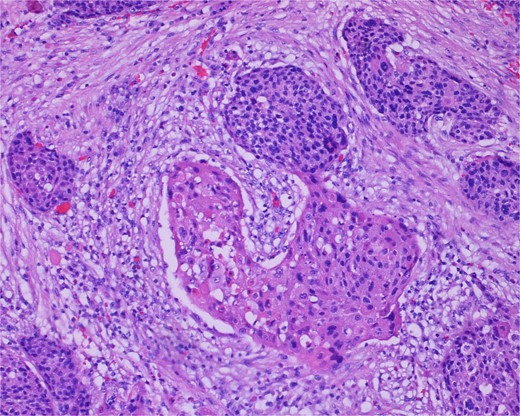

Low-power view of the neoplasm shows urothelial carcinoma on the left and neuroendocrine carcinoma on the right of the image.

The gross specimen consisted of multiple particles of gray friable tissue, aggregating to 58 g, 8 × 8 × 4 cm in greatest dimensions. Representative sections were submitted for histological processing and subsequent microscopic study in 12 cassettes. Histopathologic examination of the curated bladder mass revealed sheets of high-grade malignant urothelial carcinoma with adjacent areas of neuroendocrine-like differentiation (Fig. 1). There were extensive areas of tumor necrosis, extending into the muscularis propria. Merging of divergent differentiated cells was discernible in some areas (Fig. 2). Immunohistochemical stains of malignant neuroendocrine cells (Fig. 3) were positive for CD56, NSE, synaptophysin, INSM1, GATA-3 (scant), and Ki-67 (>80%), but negative for chromogranin A, TTF-1, p53, uroplakin, and Pan-CK. The malignant urothelial cells were positive for GATA-3 (Fig. 4). The histologic and IHC profiles of the curated bladder mass were consistent with invasive high-grade urothelial carcinoma, with neuroendocrine carcinoma comprising ~30% of the malignant cells.